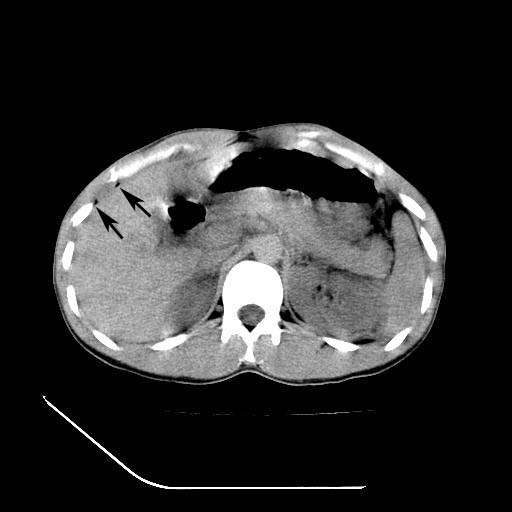

m-25y 高空堕落 12 月5号

12月7号病人尿量200ml/24h 急查双肾ct

左肾挫裂伤并肾周血肿;

左肾挫裂伤并肾周血肿

支持 : 左肾挫裂伤并肾周血肿

支持:1、左肾挫裂伤并肾周血肿;

2、少量腹水;

3、左肾旋转不良;

4、反射性肠淤张。

除了1:左肾挫裂伤并肾周血肿;

2:少量腹水

第二次ct检查后:临床医生腹水穿刺后考虑肠系膜动脉破裂,后实行剖腹探查:于空肠距离十二指肠90cm处发现肠管破裂,破裂口较小;修补后关腹。